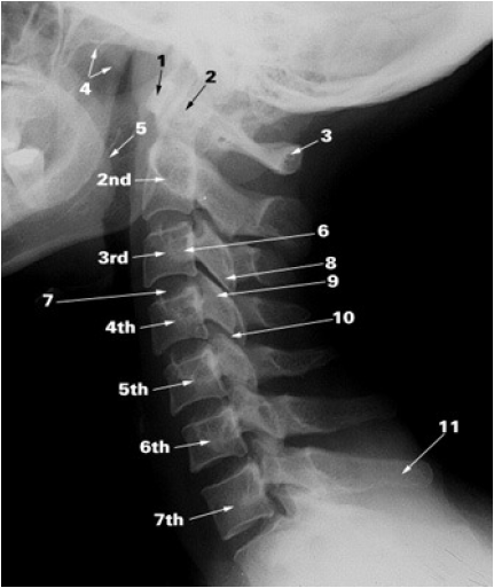

Anatomical Landmarks

- Mastoid tip- 1cm below and anterior-C1

- Hyoid bone – C3

- Thyroid Cartilage – C4-5

- Cricoid cartilage – C6